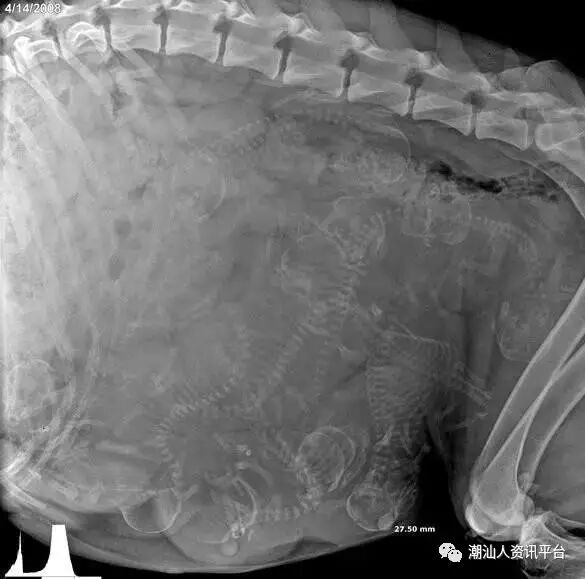

怀孕的母狗,满肚子的小生命。